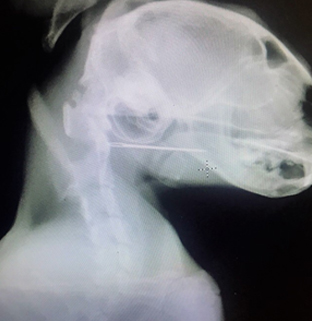

В качестве дополнительной диагностики был проведен рентген шейного отдела, в результате которого было выявлено инородное тело – игла в верхней части пищевода.